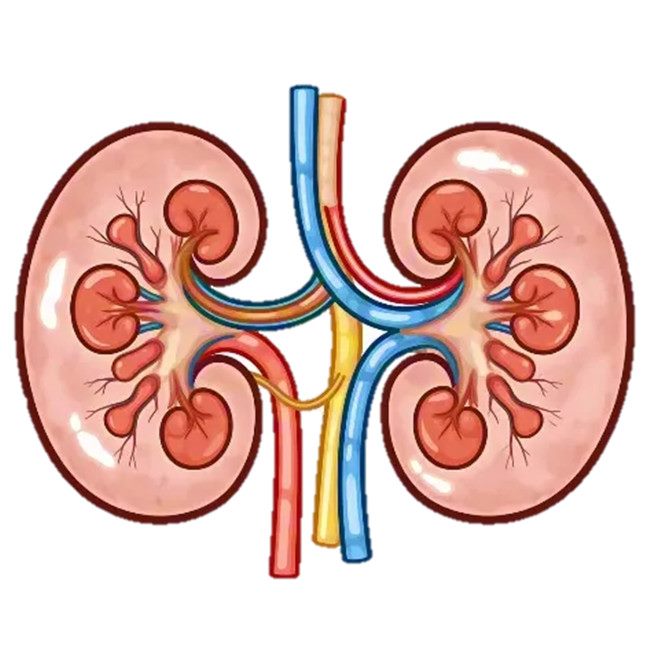

肾脏

学名:肾脏

形状:蚕豆状,左右各一

位置:腹膜后脊柱两侧

大小:长10-12cm,宽5-6cm,厚3-4cm,重120-150g

结构:由100万个肾单位和大量血管、神经纤维等组成